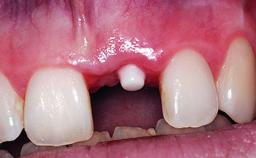

Replacement of a Compromised Upper Right Central Incisor: Hard- and Soft-tissue Augmentation, Late Placement of an RC Bone Level Implant

A 36-year-old male patient with a compromised maxillary central incisor was referred by his general dentist for consultation. The patient’s chief complaints were the gradual debonding of a temporary crown on the right central incisor and unsatisfactory esthetics due to an increasing diastema between the right central and lateral incisors. The patient reported a traumatic event some years previously, when a crown had been placed after root-canal treatment. The referring dentist wanted to provide a new crown restoration, but was concerned about the condition of the residual root. Anamnesis was negative for any other dental or periodontal pathology in the remaining dentition. The patient reported taking no medications: He was a smoker (10 to 15 cigs/day) and had realistic esthetic expectations.

Placement Protocol Early or late implant placement

Loading Protocol Conventional or early

Interim Prosthesis during Healing Removable Removable